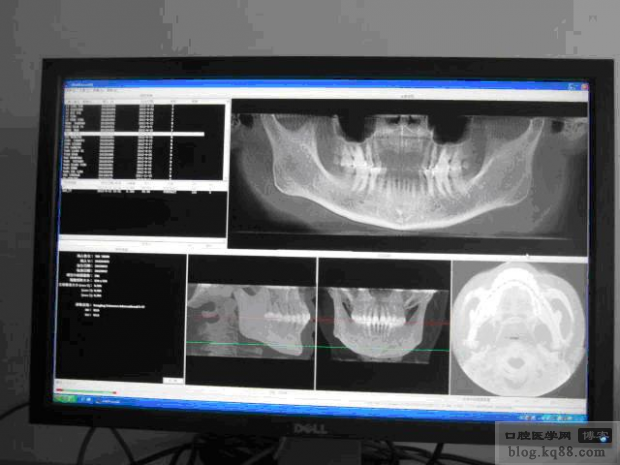

圖2是患者重建后CBCT的初始頁面

圖2